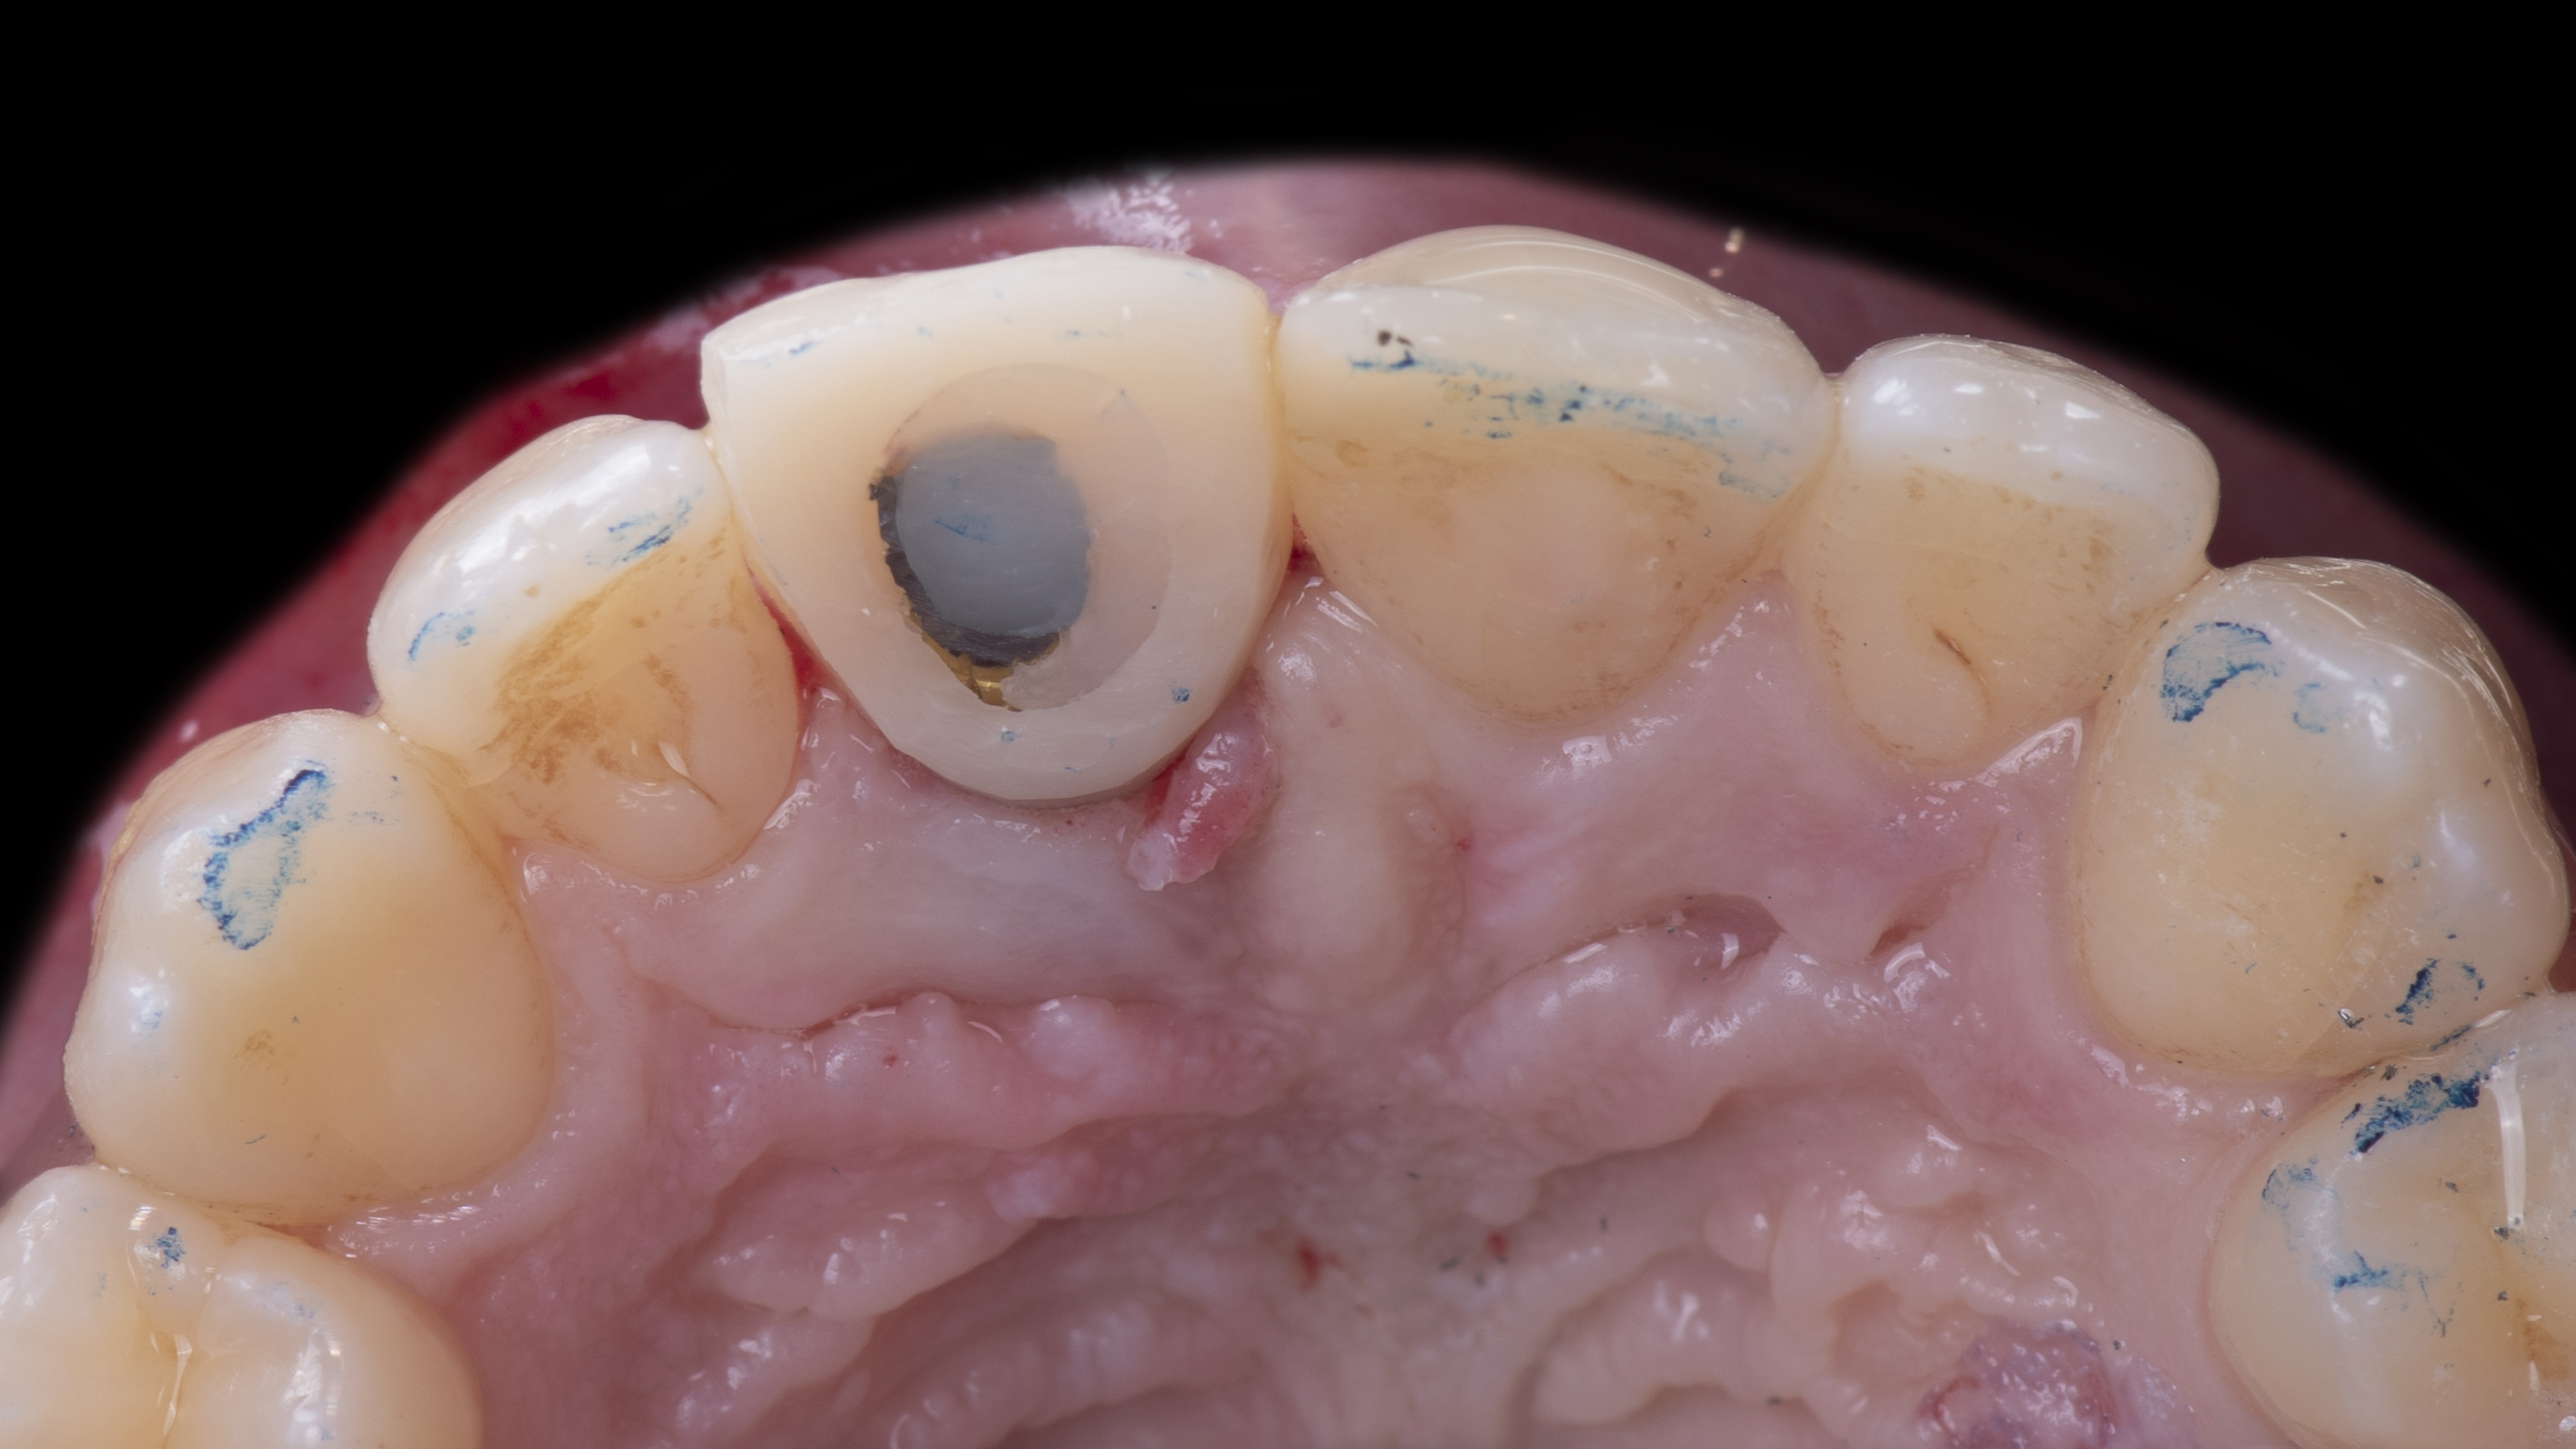

A l’examen clinique on s’aperçoit que la dent 11 est légèrement sur dimensionnée et présente une dyschromie (photo 1).

Une copie de la couronne de la patiente est imprimée et évidée pour permettre de la positionner correctement. Elle est ensuite solidarisée à un pilier provisoire vissé dans l’implant. Ceci nous permet ensuite d’ajuster le profil d’émergence (Photo 12).